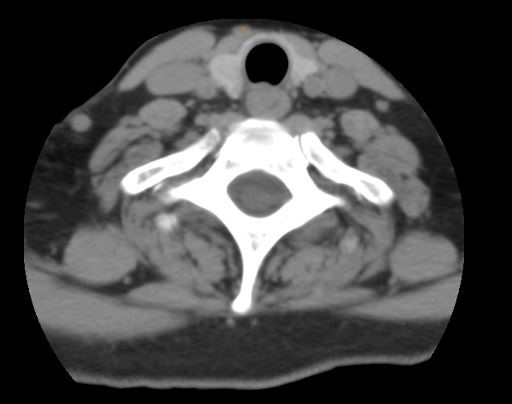

CT Scan C7T1

Her flexion extension x-ray showed a 2 mm anterior slip at C7/T1 which he felt was not severe enough to warrant surgery.   NCV testing concluded a right radiculopathy and left peripheral neuropathy.  The surgeon concluded that it was a right C6/7 radiculopathy and a left ulnar peripheral neuropathy.